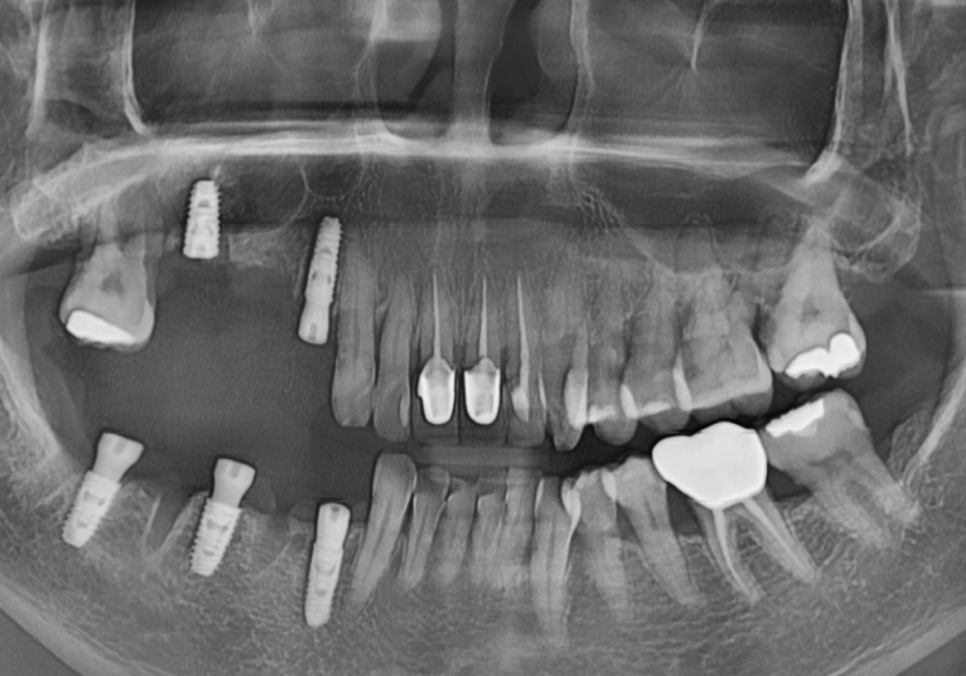

위쪽 어금니 부위는 뼈가 너무 부족해서

잇몸뼈 위쪽의 빈 공간인

251201

상악동을 들어 올리고 뼈를 채워 넣는

상악동 거상술을 병행하며

임플란트를 식립했어요.

260112

아래쪽 어금니와 앞니 부위도

광범위한 뼈이식과 함께 임플란트를

식립했습니다.

남은 치아들을 살리기 위해

잇몸 깊숙한 곳까지 청소하는

잇몸 치료를 병행했습니다.

고령의 환자분이신 점을 고려해

무리가 가지 않도록

오른쪽부터 단계별로 진행하여

임플란트 치료를 마무리했습니다.